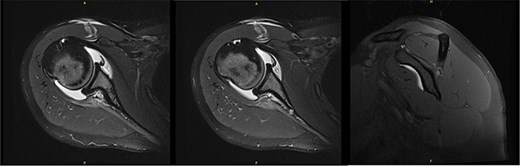

An 18-year-old, right-hand dominant woman presented reporting several weeks of right shoulder pain limiting participation in DIII collegiate volleyball. Examination revealed atrophy of the infraspinatus region. Muscle testing revealed weakness of infraspinatus and supraspinatus with reproducible symptoms. Radiographs were without transverse scapular ligament calcification (Fig. 1). Magnetic resonance imaging (MRI) arthrogram revealed low-grade undersurface fraying of the supraspinatus and infraspinatus tendons consistent with impingement, hypertrophic posterior inferior labrum, and no evidence of paralabral cyst (Fig. 2). Rest from hitting activities, anti-inflammatory medications, and periscapular strengthening therapy were initiated.

Initial MRI arthrogram revealed low-grade undersurface fraying of the supraspinatus and infraspinatus tendons consistent with internal impingement, hypertrophic posterior inferior labrum without visible tearing, and no evidence of paralabral cyst.